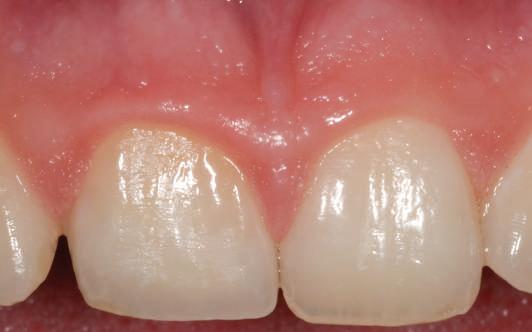

După aproximativ 10 săptămâni am hotărât protezarea preparațiilor 34 și 35 cu coroane metalo-ceamice și realizarea unei restaurări fixe metalo-ceramice înșurubate ocluzal la nivelul bonturilor intermediare de la implanturile 36 și 37.

Figurile 1. Status clinic şi radiologic iniţial; 2. Bontul Balance Base Narrow Straight GH 3.0; 3. Bonturile Balance Base Narrow aplicate imediat post-inserare la 25 Ncm; 4. Aplicarea capelor de protecţie şi sutura; 5. Stâlpii de amprentă înşurubaţi la nivelul bonturilor Balance Base Narrow;

stâlpilor montați în etapa chirugicală (abutment/tissue level impression) (fig. 5). Amprenta finală s-a realizat cu ajutorul unei linguri individuale deschise în zona implanturilor 36 și 37, folosind vinylsiloxanether (Identium, Kettenbach) într-un singur